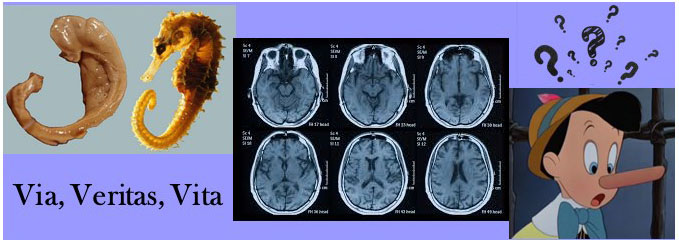

Detecting Deception

Can you detect a lie? Adjudicators of the law might question whether suspects, witnesses and/or victims are lying or accurately recalling the truth. While perceptional interpretations necessarily vary somewhat, there is only one truth that is reality. The brain is the cardinal transgressor in the commission of a crime, prescient to the realistic accounting of actions and observations.